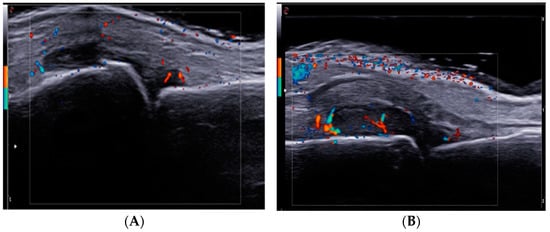

2.4. Ultrasound Examination

- Barbulescu, A.L.; Ciurea, P.L.; Mitran, C.; Chisalau, B.A.; Parvanescu, C.D.; Firulescu, S.C.; Balasoiu, M.; Boldeanu, M.V.; Popoviciu, H.; Vreju, F.A. High-frequency ultrasonography of the hand versus anti-RA33 evaluation in early rheumatoid ar-thritis—A pilot study. Med. Ultrason. 2017, 19, 166–171. [Google Scholar] [CrossRef]

- D’Agostino, M.A.; Terslev, L.; Aegerter, P.; Backhaus, M.; Balint, P.; Bruyn, G.A.; Filippucci, E.; Grassi, W.; Iagnocco, A.; Jousse-Joulin, S.; et al. Scoring ultrasound synovitis in rheumatoid arthritis: A EULAR-OMERACT ultrasound taskforce—Part 1: Definition and development of a standardized, consensus-based scoring system. RMD Open 2017, 3, e000428. [Google Scholar] [CrossRef]

- Backhaus, M.; Ohrndorf, S.; Kellner, H.; Strunk, J.; Backhaus, T.M.; Hartung, W.; Sattler, H.; Albrecht, K.; Kaufmann, J.; Becker, K.; et al. Evaluation of a novel 7-joint ultrasound score in daily rheumatologic practice: A pilot project. Arthritis Rheum. 2009, 61, 1194–1201. [Google Scholar] [CrossRef]

- Szkudlarek, M.; Court-Payen, M.; Jacobsen, S.; Klarlund, M.; Thomsen, H.S.; Østergaard, M. Interobserver agreement in ultrasonography of the finger and toe joints in rheumatoid arthritis. Arthritis Rheum. 2003, 48, 955–962. [Google Scholar] [CrossRef]